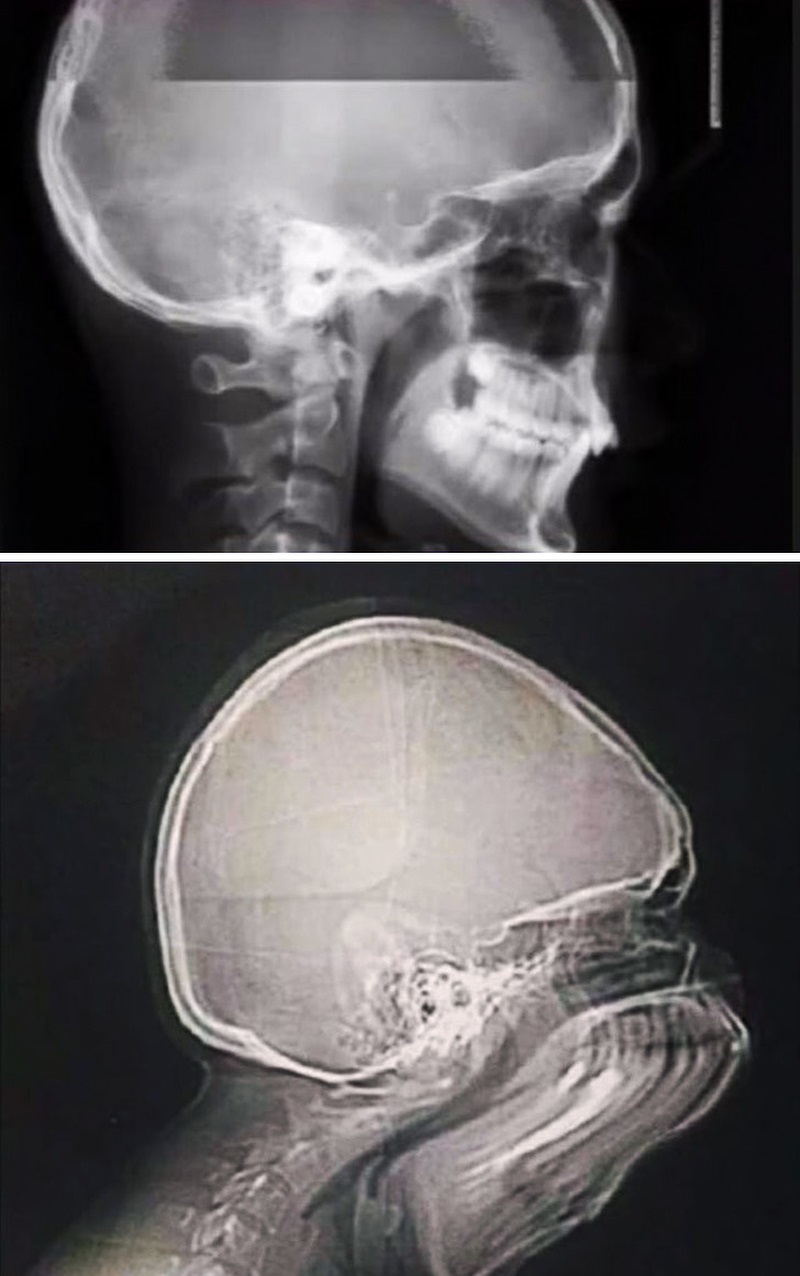

7. Ngáp khi chụp X-quang trông sẽ thế này.